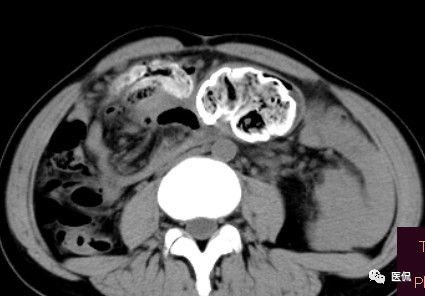

女 40岁 ,10年前做个剖腹产术。之后到现在一直感觉肚子疼,去很多医院做检查 诊断肠结核,经过反复抗结核治疗。病人10年瘦了几十斤。

腹腔内残留的纱布在人体内引起渗出或液化坏死并纤维包裹形成异物性脓肿(纱布瘤)。纱布瘤的影像特点:圆形或卵圆形肿块,较大,有完整包膜,薄壁,较少的情况下为厚壁,边界较完整,增强后薄膜可以持续强化。不同时期的纱布瘤可以有不同表现:早期(10个月或半年内)多表现为蜂窝状;2~5年内一般表现为囊性飘带状;10~20年之后则为实性软组织密度,包膜钙化呈钙化网状结构。手术过程中残留在人体内的医用纱布所形成的肿瘤样病变。

手术所见:腹腔内无腹水,肿块位于右上腹,约15x10x8cm大小 ,周围网膜包裹粘连,向胆囊三角处延续,呈囊性,与周围结构无明显浸润,仔细分离粘连,逐步游离暴露肿块,见肿块与右肾及结肠、十二指肠无明显关系,初步确定为肿大的胆囊,继续向肝门部游离,见肿块与胃窦粘连,因分离困难,决定切开肿块。穿刺肿块有黄色脓液抽出,考虑胆囊脓肿,切开囊壁,吸出大量黄色混浊脓液约1200ml,探查囊腔,见粘膜层为胆囊粘膜,腔内有一异物残留,经证实为医用盐水纱布,取出纱布约15x15cm大小,封存。继续游离胆囊至完整切除,检查囊壁无明显占位病变。

病理诊断:胆囊异物残留,胆囊化脓性炎、胆囊脓肿。

纱布团遗留腹腔后,首先由大网膜及邻近肠管将其紧密粘连并包裹,自肠管与纱布团粘连处开始逐渐向周围扩展产生纤维结缔组织包膜直至完全包住纱布团,该包膜血管丰富,充血明显,随时间延长逐渐向纱布团网眼内生长,使包膜逐渐增厚。机体还通过在包膜内产生大量异物巨细胞来围歼异物纱线,使包膜内侧形成脓肿。当包膜完全形成后,肠管与纱布团的粘连变的疏松,此时纱布团具有了一定的活动度。

腹腔内遗留纱布团的影像学表现,以B超较具特征性,其主要表现为:腹腔或盆腔内特殊率减的黑色包块,后方伴有扇形衰减的声影,上窄下宽,好似一“黑色大布”,早期包块内含有不规则光团或光点,随时间延长有缩小或消失,为纱布团内气体。CT的优势在于早期常表现为软组织密度的肿块,其内可见多少不等的气泡,随时间的延长气泡逐渐被吸收减少至消失,增强扫描可见包膜不同程度强化而内容物无强化。熟悉其影像学表现,可在术前作出明确诊断。